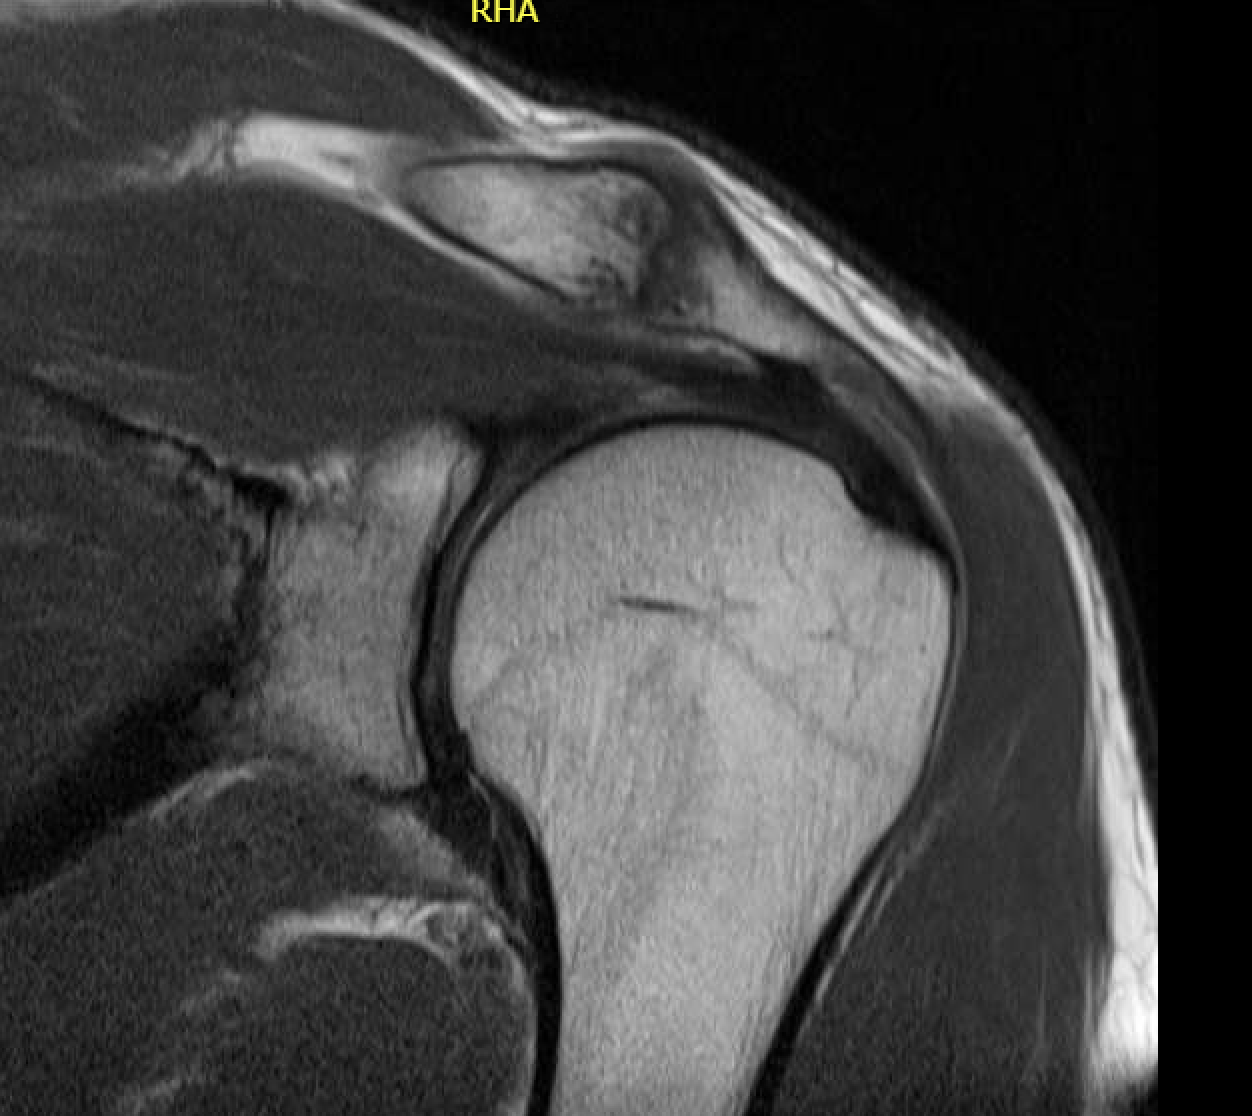

MRI

Acromioclavicular osteoarthritis

Stein et al. J Should Elbow Surg 2001

Grade I: Normal

Grade II: Capsular distension, bone marrow edema, mild joint narrowing

Grade III: Capsular distension, joint space narrowing, marginal osteophytes

Grade IV: Markedly abnormal ACJ with large osteophytes